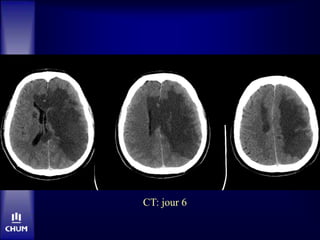

Jour 6:

• Comateux, tetraplégique

• Mydriase bilatérale

• Soins de confort

• Décès le même jour

CT: jour 6